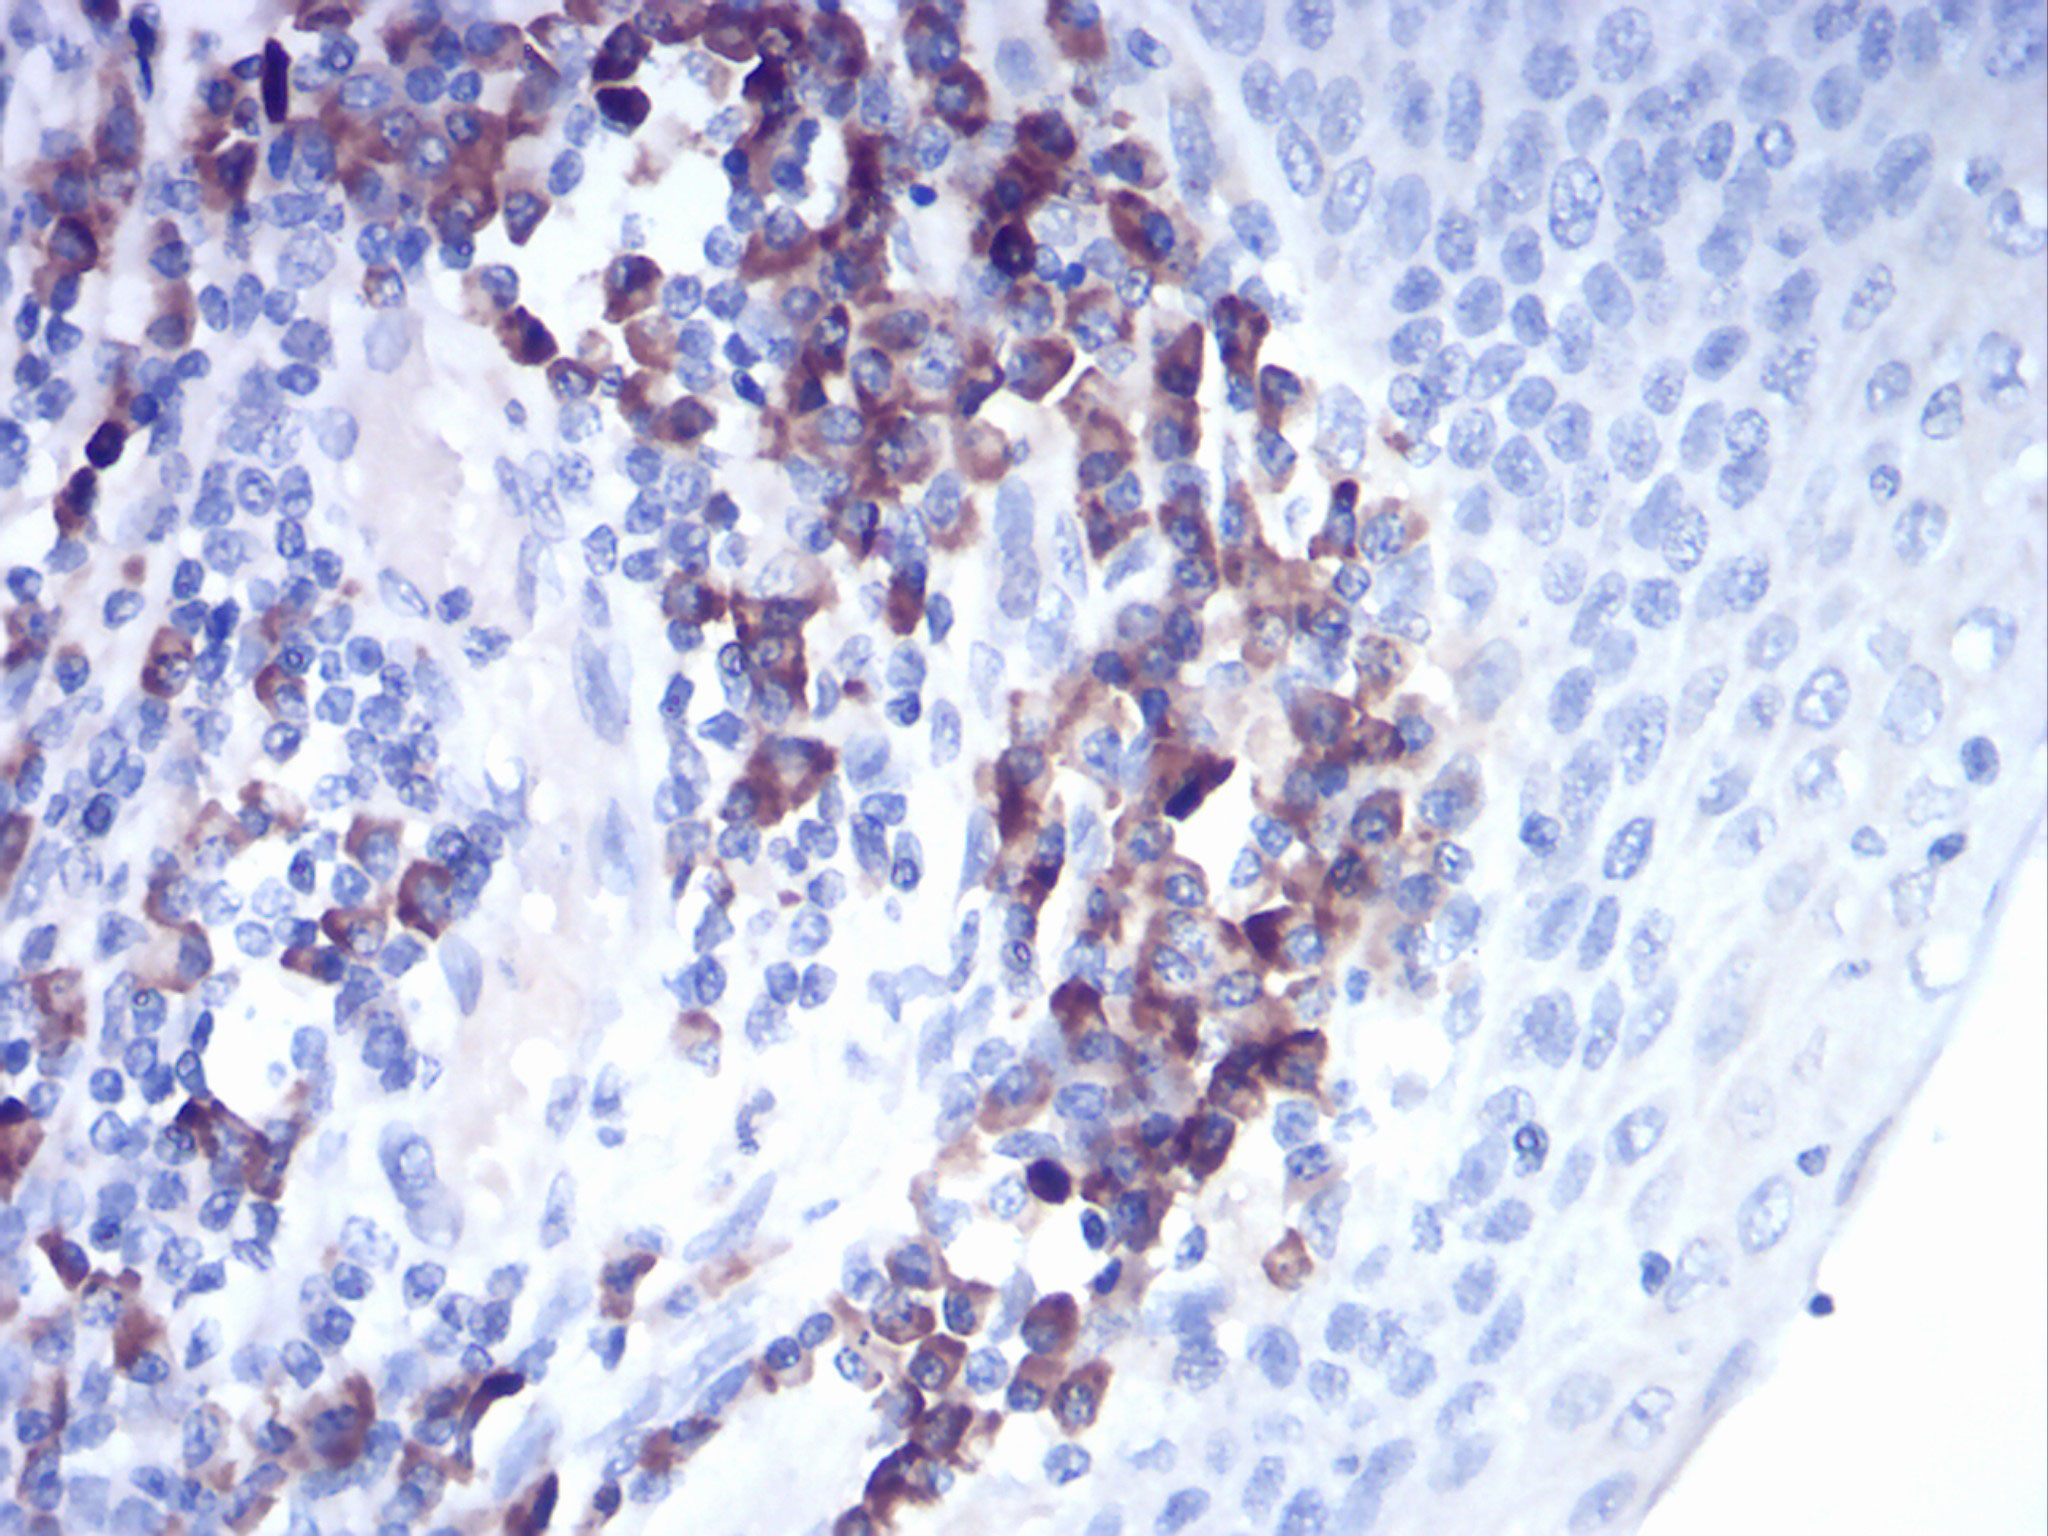

Images |

Figure 3:Immunohistochemical analysis of paraffin-embedded esophagus tissues using CTSD mouse mAb with DAB staining. |